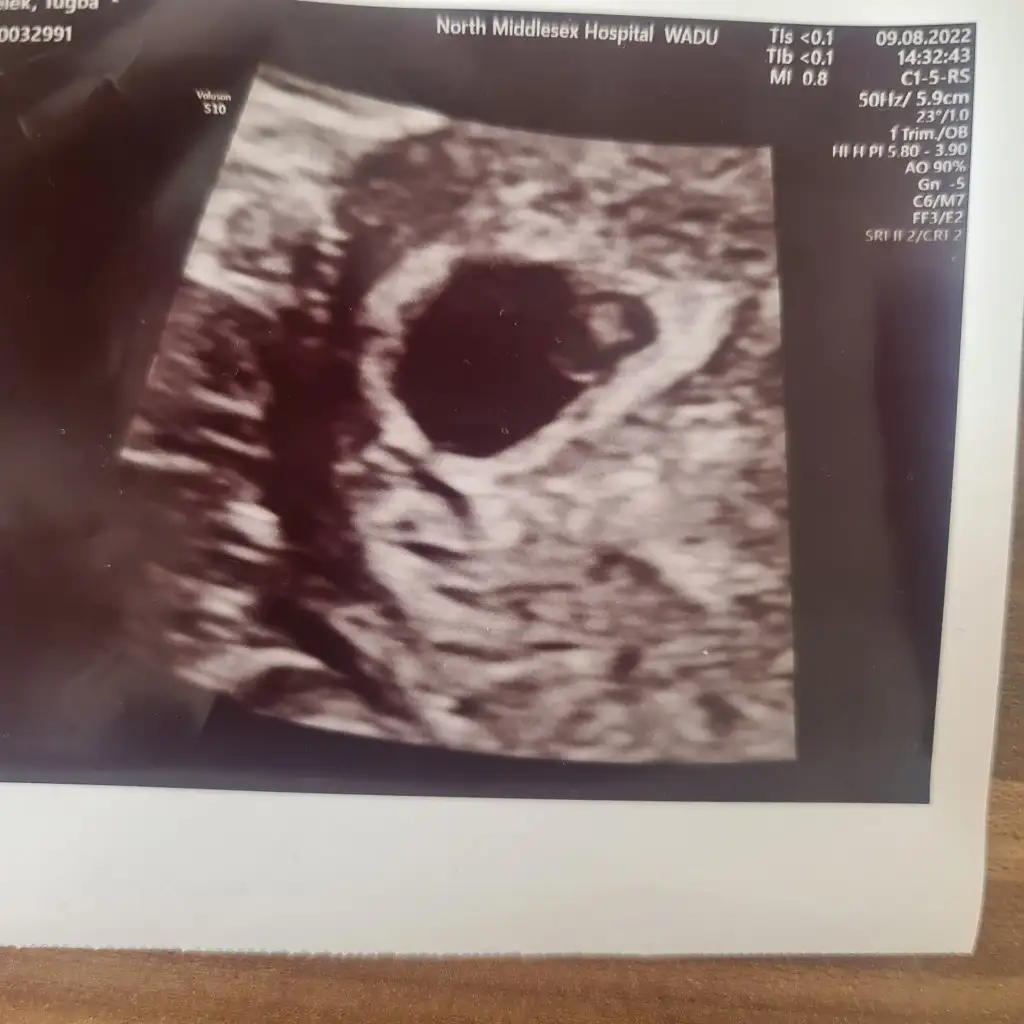

Bizim bebeğimiz içinde tahminde bulunur musunuz ?